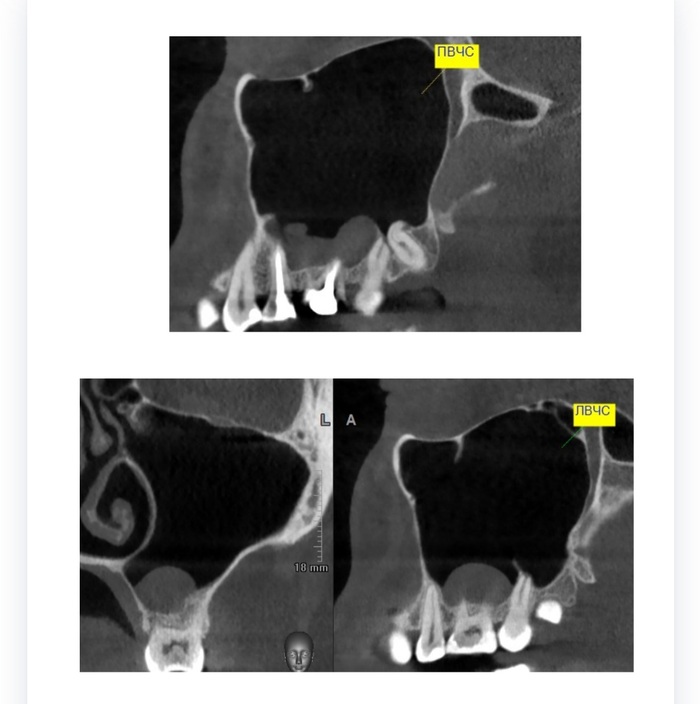

Киста: удалять или ждать⁠⁠

Здравствуйте, уважаемые пикабушники, особенно с медицинскими корочками!

У меня на кт нашли кисту. В описании указали как риногенную (я так понимаю, что в г/пазухе). При жевании на зуб (26), который прямо под ней) чувствую дискомфорт внутри щеки. Обошёл несколько лоров и стоматологов в небольшом городе Поволжья. Лоры не видят проблемы и говорят, что пока нет боли, то лезть через нос не стоит, нужно подождать. Стоматологи же говорят либо тоже ждать и ничего не делать, либо депульпировать зуб (этот вариант я не совсем понимаю, как это может помочь? Да и жалко, зуб живой.)

Вопрос поэтому такой: стоит ли съездить в крупный город и попросить удалить эту гадость через нос? Если да, то как, насколько инвазивно? Это больно и есть ли последствия? Или идти через зуб? Мб у кого-то был такой опыт?

Ждать и терпеть дискомфорт не очень хочу, тем более что сейчас у меня отпуск и есть возможность отлежаться. Боюсь, что эта киста начнёт расти или лопнет в какой-нибудь неподходящий момент, если оттянуть время.